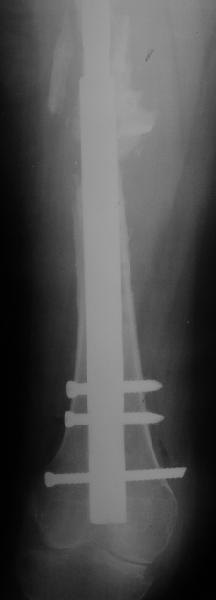

Female, rheumatoid, THA in 2003, car accident in 2006, failed plating. Nailing in Oct 2007. The nail is solid with hollow proximal part where the stem is docked. Last images are in 1 year after

nailing.

Спасибо за обсуждение. После нескольких дней тракции аппаратом сделали. Попытка закрытой репозиции не удалась из-за смещения по ширине, мешали фрагменты цемента. После их удаления репозиция получилась. Еще убрали немного цемента с ножки по латерльной стороне, чтобы обнажить 40-50 мм ее дистальной части, для плотной посадки гвоздя. Дальнейшее введение гвоздя было несложным. Протез показался нам стабильным в проксимальной части как латерально, так и медиально. Картинки в приложении.

THX for the discussion. After few days of traction by ex-fix the surgery was performed. An attempt of closed nailing was unsuccesful because of fragment translation, which was blocked by cement fragments. After removal of broken cement pieces reduction was reached "automagically". Also some cement from lateral part was removed by

chisel to expose distal 40-50 mm of the stem to allow tight fit of the nail. Further fixation by the nail was pretty easy and straightforward. Images attached. The stem looked stable in its proximal part both laterally and medially. Comments/critics are welcome.

Reminded me of a case I did a couple years ago - 30 year old woman with juvenile rheumatoid arthritis and a nonunion below her stem. Fixed with retrograde nail which docked with the stem and a lateral locking plate. Image attached. One of the companies should come up with a stem design and nail system that anticipates this need.